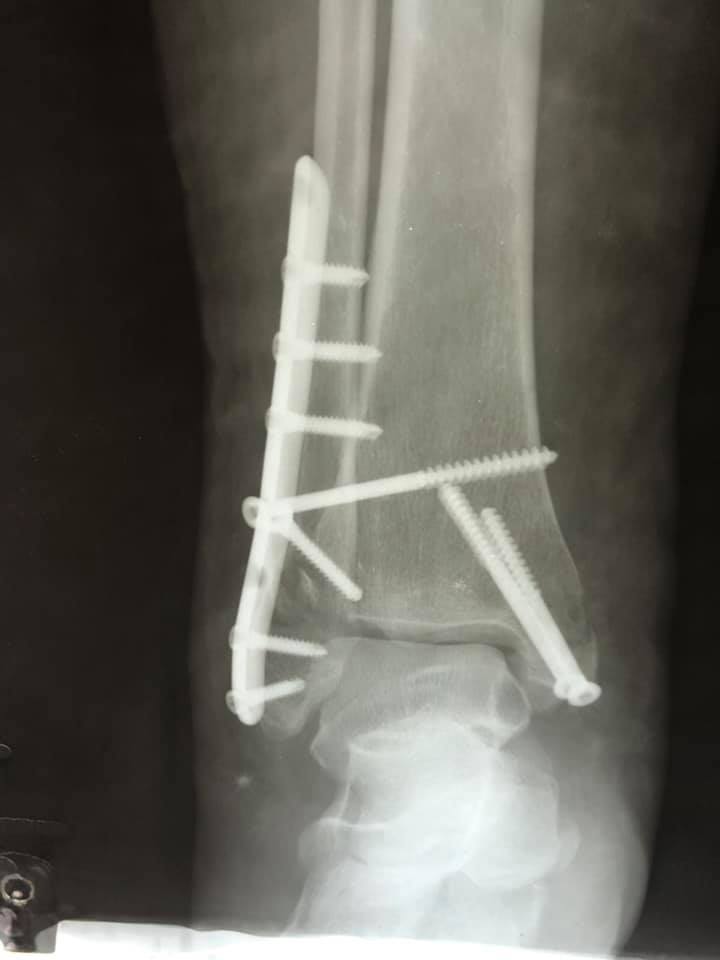

Завдяки вчасному зверненню та професіоналізму лікаря-ортопеда-травматолога, жінку вдалося врятувати. В ургентному порядку жінку доставили в КНП «НЦМЛ». Після огляду лікар встановив діагноз: відламковий перелом кісточок гомілки з вивихом стопи.

Пацієнтці виконали відкриту репозицію уламків з внутрішньою фіксацією. Операція пройшла успішно.